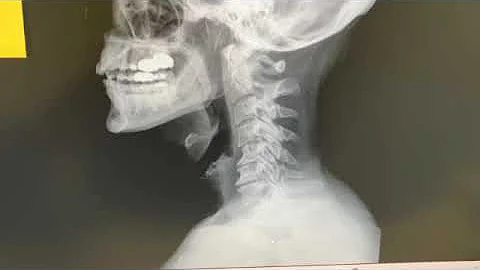

Is Spinal Degeneration Causing Autoimmune Thyroid Disease? A Root Cause Doctors Are Ignoring.

ROOT CAUSE OF OVERCOMING THYROID DISEASE & AUTOIMMUNITY! In this video I share groundbreaking research doctors ...